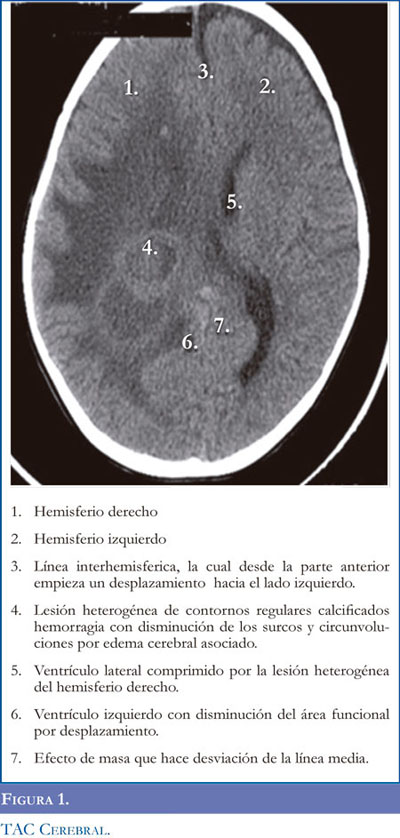

En los estudios imaginológicos iníciales se destacó en la tomografía axial computarizada (TAC) cerebral una hemorragia cerebral secundaria a una malformación cavernomatosa central ubicada en el lóbulo frontal y parietal derecho (Figura 1). Para ampliar la información se realizó resonancia magnética (RMN) donde se evidencio un compromiso multifocal por lesiones hemorrágicas que involucran los compartimientos supratentoriales frontoparietal derecho y tenía forma serpentiforme rodeada por edema vasogénico (Figuras 2-3).

Los angiomas cavernosos del SNC son lesiones vasculares angiográficamente ocultas. Pueden ser clínicamente silenciosas o anunciar su presencia con convulsiones, cefaleas o déficit neurológico (5-10). La presencia clásica de imágenes por RM, semejantes a 'palomitas de maíz' con un núcleo reticulado bien delimitado, de señal mixta por el sangrado en distintos estadios de evolución. En la TAC cerebral los angiomas cavernosos generalmente aparecen como lesiones focales nodulares que muestran leve a moderada hiperdensidad, con calcificación hasta en un 33%. La arteriografía suele ser negativa, debido a un flujo sanguíneo lento (10-13). Hecho evidenciado en este reporte de caso.